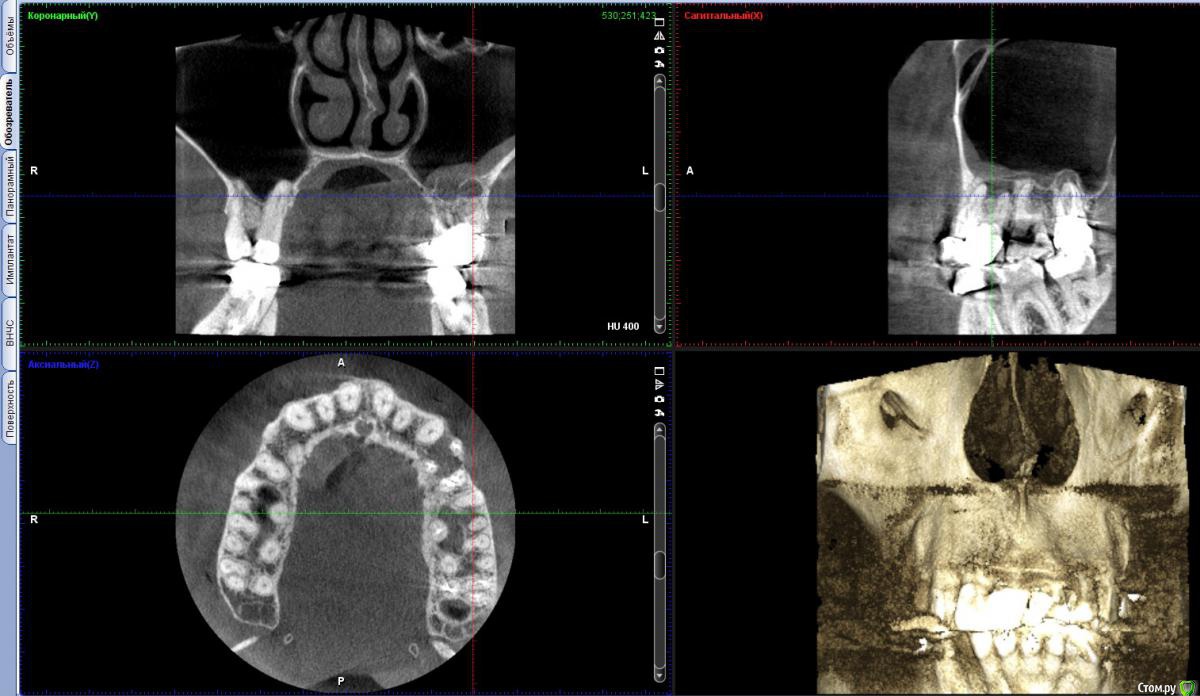

vitavita Опубликовано 4 февраля, 2015 Поделиться Опубликовано 4 февраля, 2015 Начну историю о 6 зубе с самого начала. Когда то давно - лет 30 назад , в советское время мне его кто то лечил , уже не помню кто и как, школьником был. Видимо были удалены нервы. Он меня не беспокоил практически никогда. На обычных ортопанорамных снимках ничего не видно было. 11 лет назад , перед тем как ставить на него коронку , мой доктор пытался пройти каналы, удалось только у принебноого пройти а у 2-х внешних не удалось . Долго пытался , сверла грелись и изнашивались. Сказал что материал там как стекло. Что если когда нибудь заболит то надо будет операцию делать сбоку для резекции корней. Шло время - зуб не болел , я на него нормально жевал и жую до сих пор. Вспоминаю только как то года 3 назад очень жесткое что то попалось и поболел пару дней и прошел. Не придал значения. И вот в ноябре 2014 у меня вдруг обнаружилась киста но на 4-м верхнем левом зубе - нарвало после небольшого ударо по нему сбоку. Хотя ничего не болело. Пошел естественно к врачу . На обычном ортопанорамном снимке толком не видно было. Поэтому отправил доктор меня на томограмму по поводу 4-го зуба и заодно и 6-го , т.к. помним что каналы там не были пройдены. И вот 21 ноября сдел томограмму (если интересно https://yadi.sk/d/Th2NbfMSeULRo). И на ней увидили большую кисту за 4 зубом и кисту у 6-го. Доктор предложил мне удалить 4-й , сделать резекцию 6-го с возможным синус-лифтингом и небольшую резекцию 5-го. И все это одновременно. Напугал возможным гайморитом с очень тяжелыми последствиями. Расстроившись я пошел к другому знакомому хирургу в один из стоматологических институтов. Он предложил сразу сделать резекцию 4-го зуба . Она была удачно проведена открытым способом. 2 месяца походил с йодоформной турундой (менял каждые 10 дней) . Все практически заросло. Теперь спустя 2 месяца встал вопрос о 6 зубе- как с ним быть. Посмотрев томограмму , посоветовашись с другим врачем сказал что все таки резекцию здесь делать нецелесообразно , т.к резать придется 2 корня под корешок , от зуба мало что останется и он долго не простоит. Не жилец. Надо удалять и потом как то протезировать. Послал к терапевту - может можно пройти . Терпавт сказал что для этого надо снимать коронку , но зуб то не болит. Ситуация дурацкая. Отправили к ортопеду , тот сказал что смысла снимать коронку нет , т.к. скорее всего лучше не сделают , а мучаться мне много и никакого результата. Зуб не качается , стоит твордо. И т.к через полгода мне повторно надо будет делать томограмму из-за 4 зуба , то посмотреть динамику развития и кисты и от этого делать выводы. На этом вроде остановились. Теперь у меня 2 выхода :1. или подождать полгода и потом скорее всего удалять2. идти к другому доктору и попытаться сделать резекцию 6-гоСтоит ли бороться за зуб , который к тому же не болит ? Ссылка на комментарий

vitavita Опубликовано 8 февраля, 2015 Автор Поделиться Опубликовано 8 февраля, 2015 Надо эндодонтически лечить все 3 зуба4-ому уже резекцию сделали , удалили кисту (большая была - 1см). Вроде такого размера только операцией можно удалить. 5-й тоже поскоблили заодно, но без резекции. Все уже заросло нормально за 2 месяца. Так что с этим уже проблем никаких не должно быть. А вот с 6-м проблема - доктор 11 лет назад пытался пройти каналы , но там стекло говорит. Непроходимые. Зуб под коронкой. Чтобы проверить можно ли пройти еще раз надо снимать ее. Ортопед отсоветовал - намучитесь, а пройти скорее всего не сможете. Велел наблюдать просто. Делать же резекцию один хирург говорит не надо , т.к. зуб не проживет долго , опираться уже не на что будет. А другой все таки предлагает сделать резекцию 2 корней с вычисткой кисты.Вопрос - насколько есть вероятность все таки попробовать пройти каналы если там что то вроде стекла? Может кто то посоветует в Москве действительно хорошего эндодонтолога ? Ссылка на комментарий